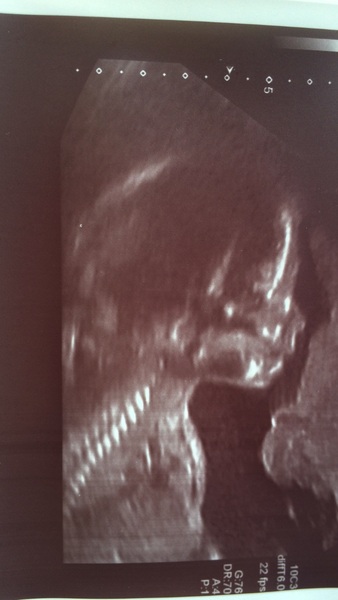

Everything went fine this afternoon :) such an amazing thing to see!

Lovely scan pic Bristol and great news Smile

Scan picture looks good Bristol